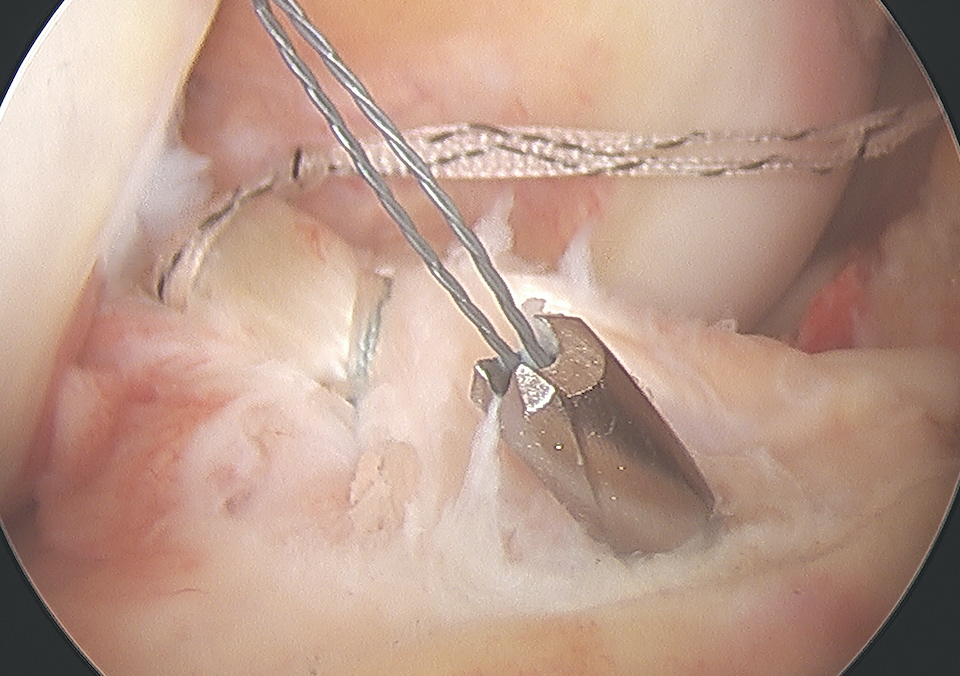

Arthroscopic suture fixation

Fragment flipped and insertion debrided Avulsion fragment reduction Passage of two loop sutures with scorpion

ACL tibial jib with beath pin Beath pin cannulated, loop wire passed Retrieval of sutures

Technique

Clean haematoma, ensure can reduce fragment with probe

- can consider temporary fixation with K wire

- arthroscopic suture passer (i.e. arthrex knee scorpion)

- pass sutures x 2 through ACL above bony fragment

- cannulas can be useful for suture management

Reduce fragment and hold with ACL tibial guide

- medial tibial incision, pass beath pins x 2 (preferable cannulated)

- 1 cm between tunnels

- beath pins exit through bony fragment

- retrieve sutures

- reduced fragment, knee in full extension

- tie over bony bridge or over cortical button

Technical note

1. Passing sutures anterior to the bony fragment rather than through may help anatomical reduction

2. Companies make cannulated beath pins, allowing suture loops to be passed up the pins